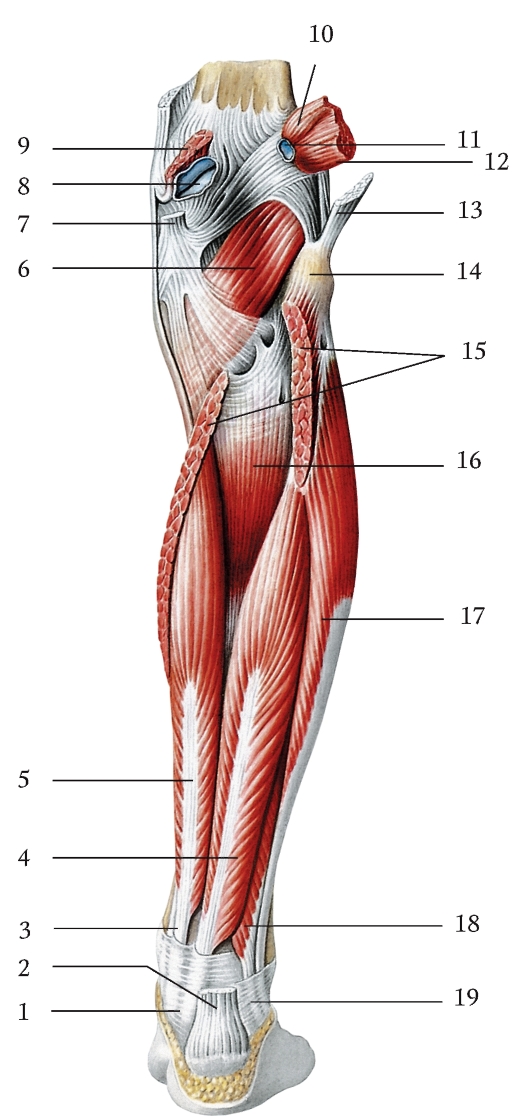

Анатомия подошвенной мышцы голени: подробное рассмотрение